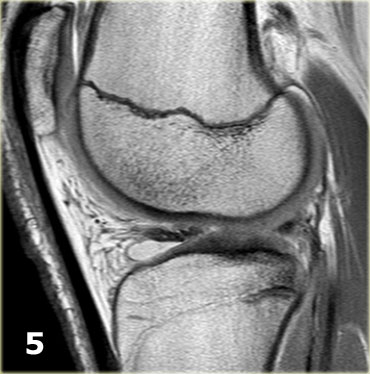

Như bạn đã đoán được qua tiêu đề của đoạn này, đây là một trường hợp sụn chêm lật (flipped meniscus).

Sụn chêm lật là một dạng đặc biệt của rách dạng quai xô (bucket-handle tear).

Sụn chêm lật xảy ra khi mảnh vỡ của sừng sau bị lật ra phía trước, khiến sừng trước của sụn chêm có vẻ to hơn bình thường.

- Sừng sau quá nhỏ và sừng trước có vẻ to hơn với đường viền không đều.

- Thoạt nhìn có vẻ như có một đường rách dọc ở sừng trước, nhưng thực chất phần sau của cấu trúc này chính là phần lật của sừng sau bị rách.

Cấu trúc phía trước là sừng trước.

Cũng cần lưu ý tình trạng phù tủy xương khu trú và dấu ấn lõm sụn khớp. - Cấu trúc phía trước là sừng trước.

- Một số bất thường ở phần sau.

- Phần sau di chuyển về phía đuôi (caudal).

- Trong hố gian lồi cầu là điểm nối giữa mảnh di lệch và phần còn lại của sừng sau.